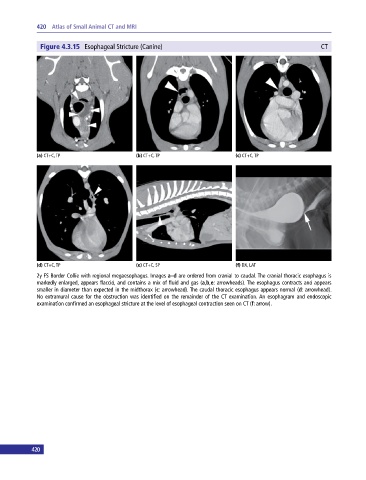

Figure 4.3.15 Esophageal Stricture (Canine) CT

(a) CT+C, TP (b) CT+C, TP (c) CT+C, TP

(d) CT+C, TP (e) CT+C, SP (f) DX, LAT

2y FS Border Collie with regional megaesophagus. Images a–d are ordered from cranial to caudal. The cranial thoracic esophagus is

markedly enlarged, appears flaccid, and contains a mix of fluid and gas (a,b,e: arrowheads). The esophagus contracts and appears

smaller in diameter than expected in the midthorax (c: arrowhead). The caudal thoracic esophagus appears normal (d: arrowhead).

No extramural cause for the obstruction was identified on the remainder of the CT examination. An esophagram and endoscopic

examination confirmed an esophageal stricture at the level of esophageal contraction seen on CT (f: arrow).